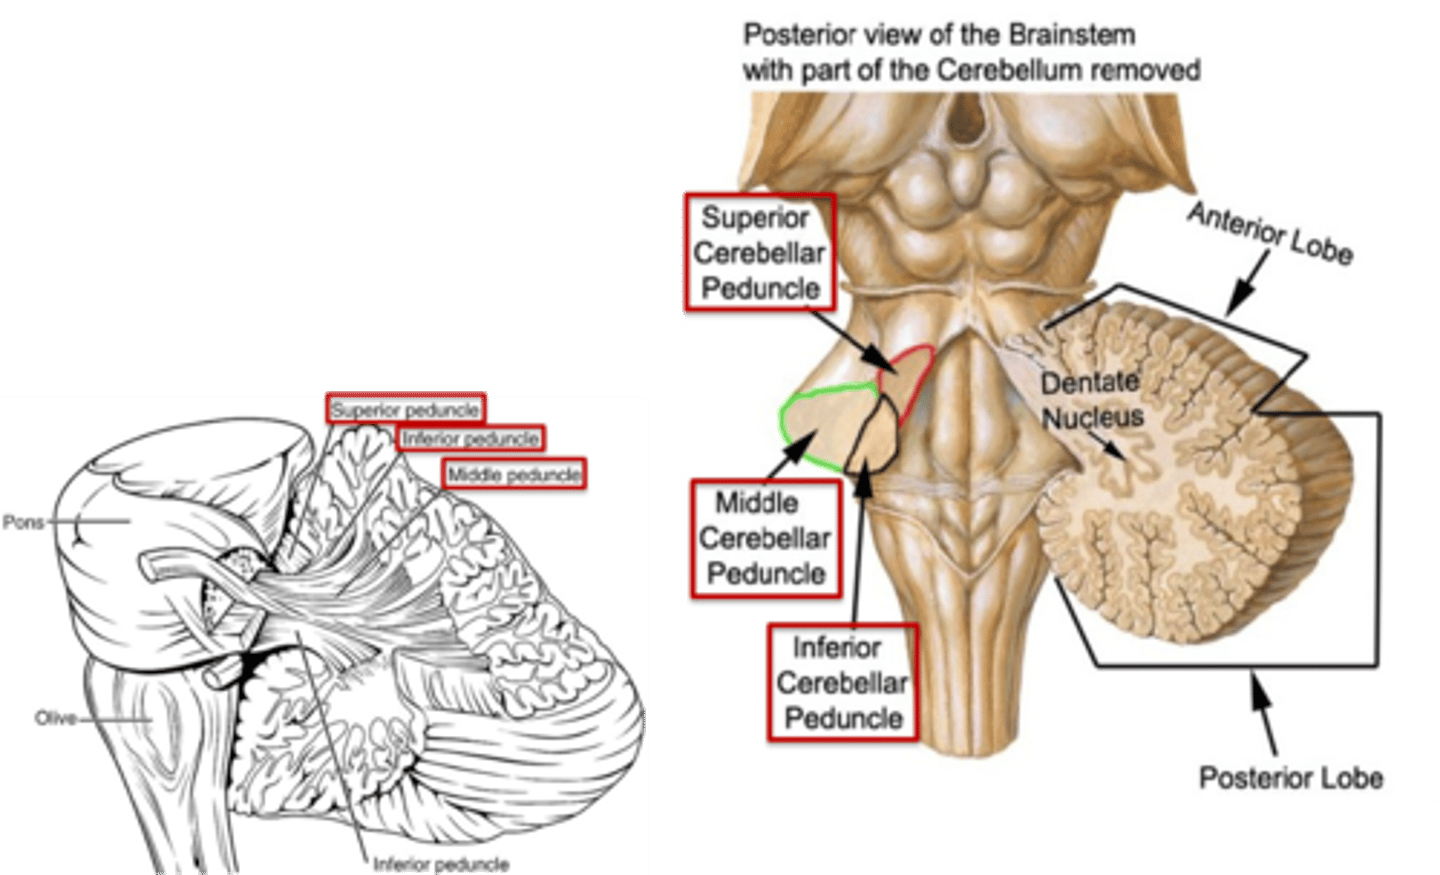

what region of the brainstem contains the cerebellar peduncles (to connect the cerebellum to the brainstem)?

pons